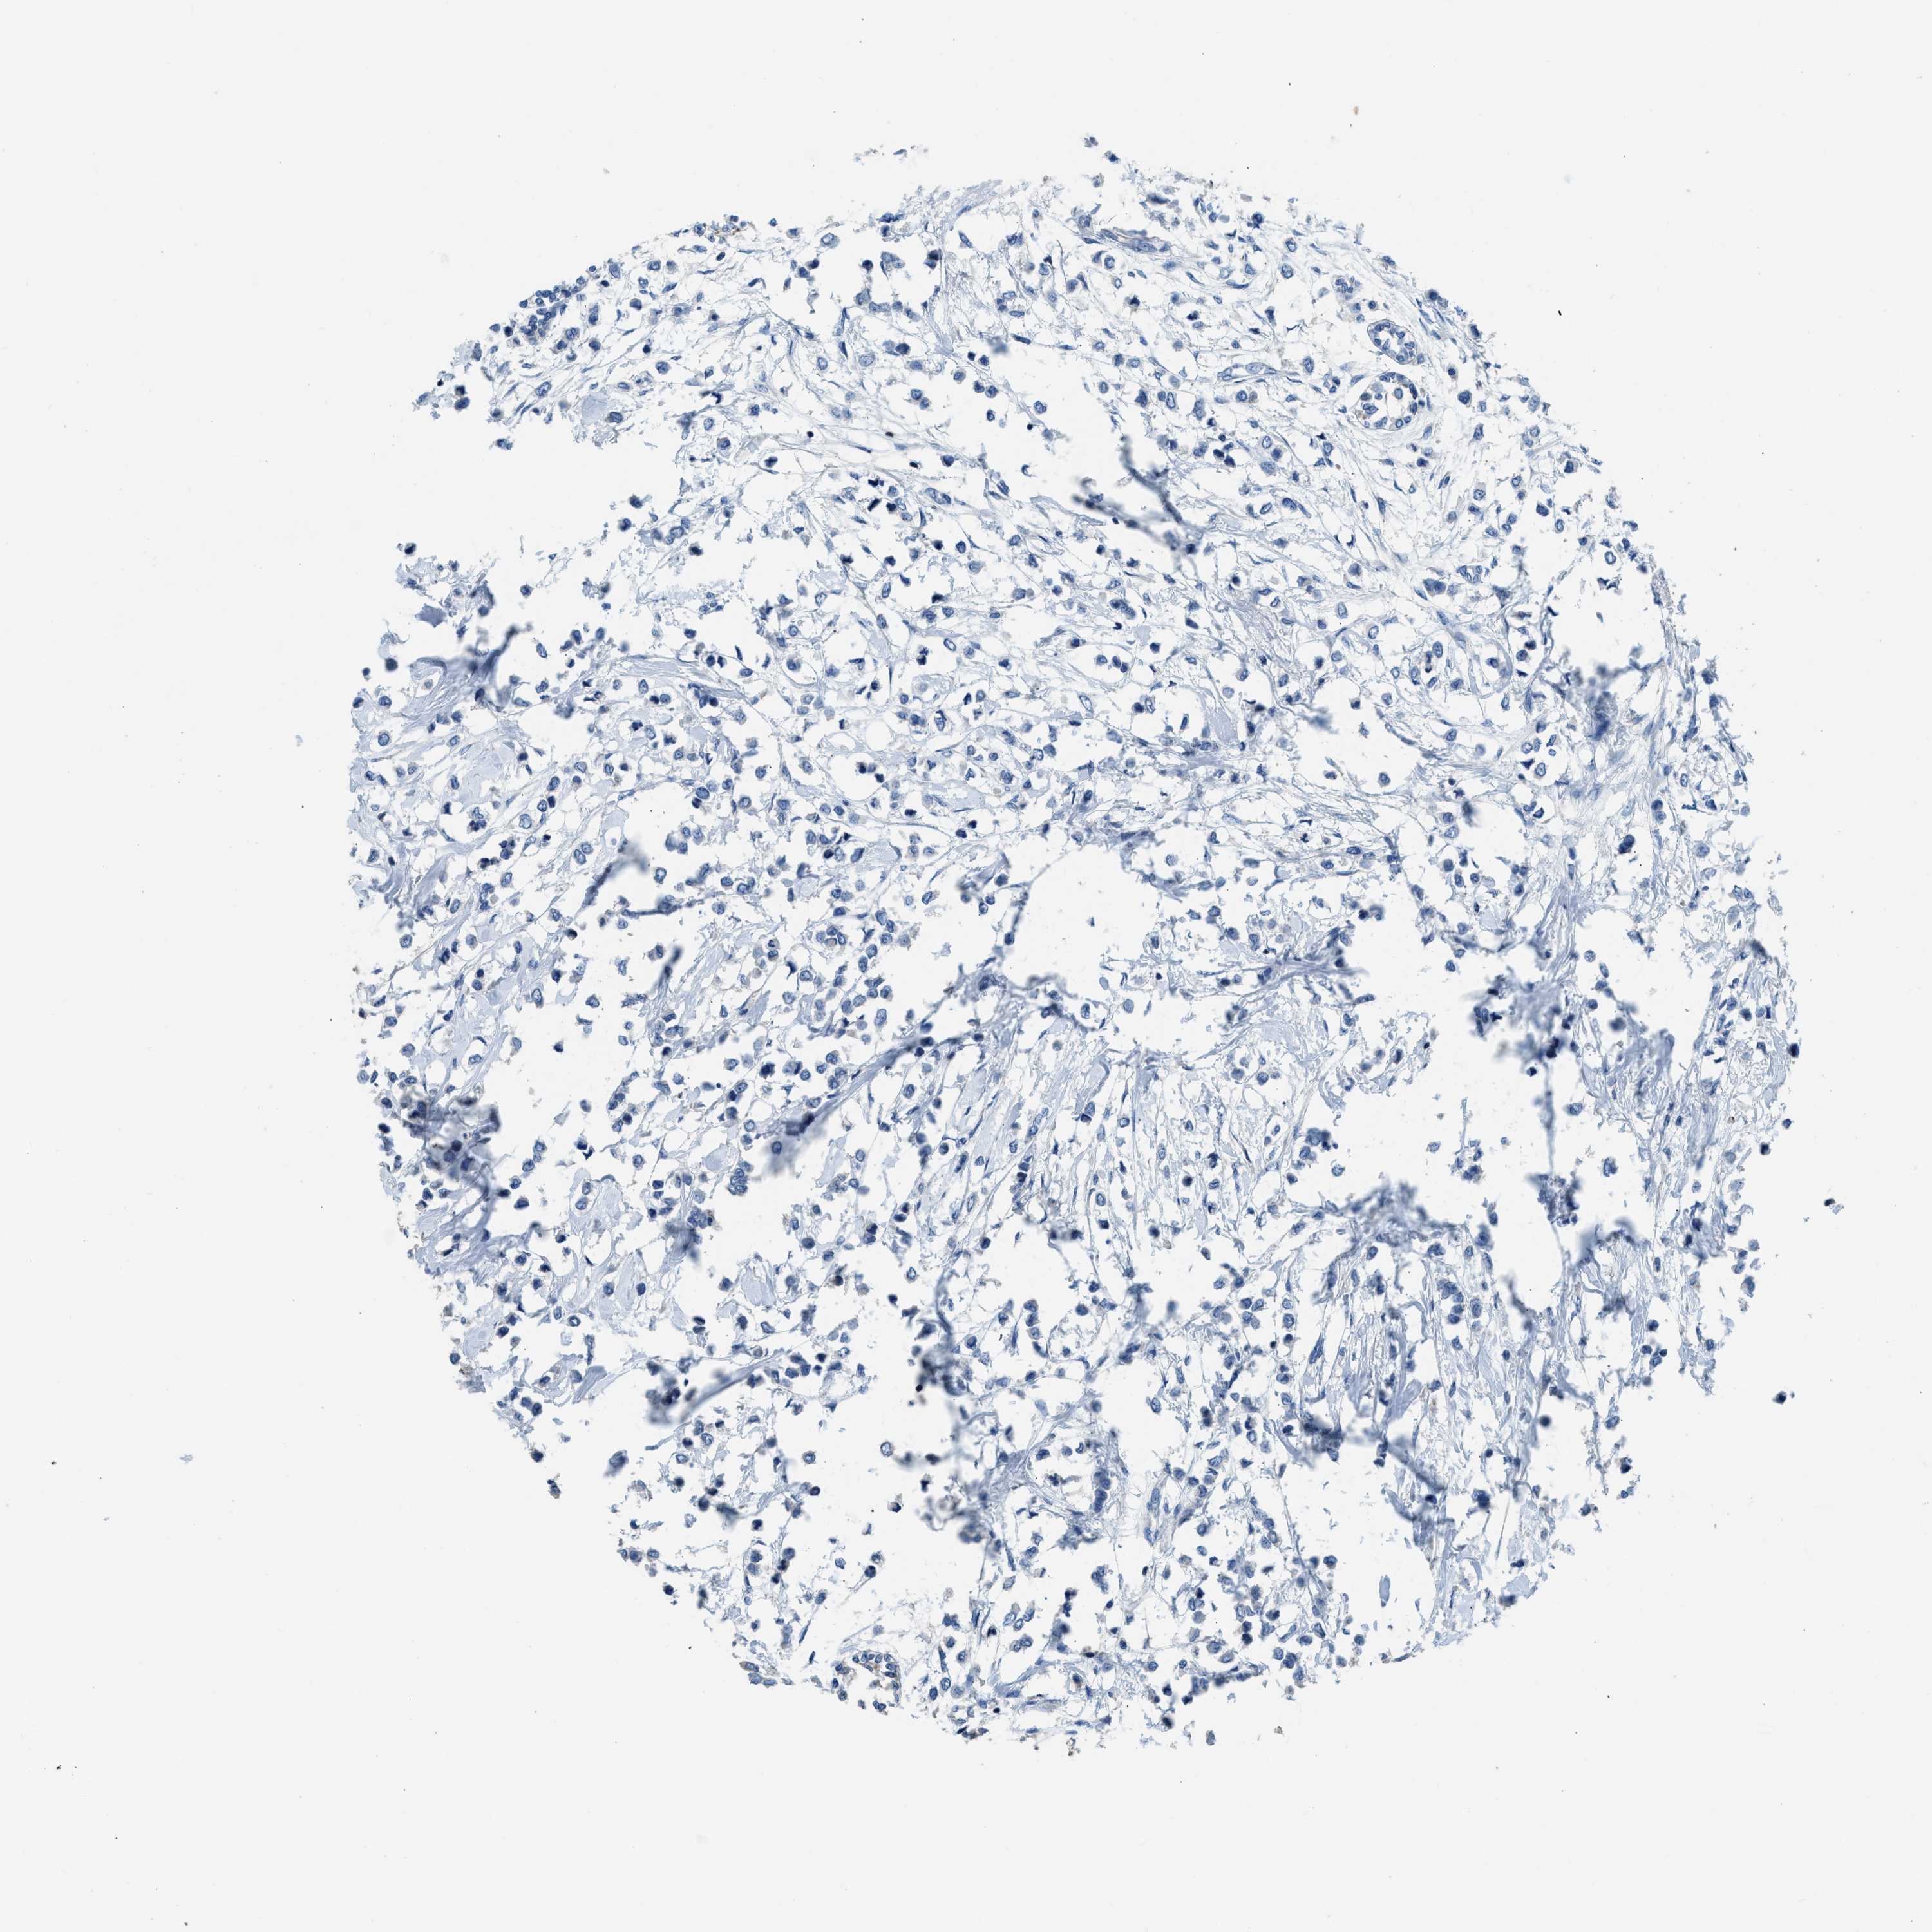

CANCER BREAST CANCER Show tissue menu

BRCA TCGA BRCA VALIDATION PROTEIN EXPRESSION

ANTIBODIES

AND

VALIDATION